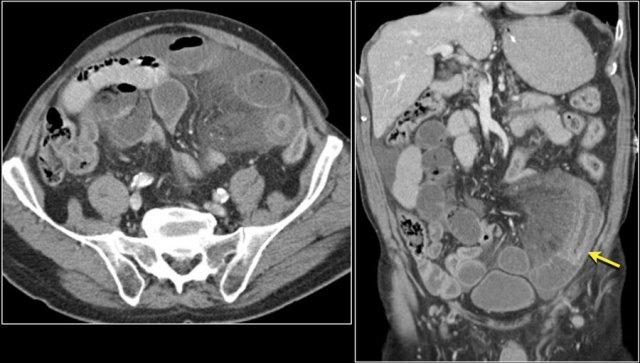

Tái phát bệnh sau phẫu thuật cắt bỏ GIST với hình ảnh các tổn thương di căn gan giảm tỷ trọng và một khối di căn phúc mạc lớn không đồng nhất.

Đây là bệnh nhân u hắc tố di căn.

Hình bên trái cho thấy lồng ruột hồi-hồi do tổn thương di căn.

Hình bên phải cho thấy lồng ruột trên mặt phẳng coronal, cùng với một hạch bạch huyết mạc treo phì đại (mũi tên vàng) và di căn gan lan rộng.